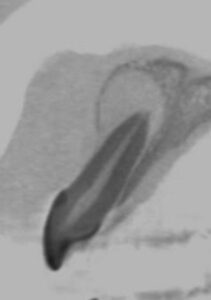

CT画像では顎骨は歯根を取り囲むように大きく吸収されており、嚢胞の完治は容易ではないことが推察されました。

そこで、治療は長期に及ぶことを説明し、「根管治療による嚢胞の縮小」⇒「外科的歯内療法による嚢胞の完全摘出」の2段構えの戦略を立てました。

ちょうど、 抗がん剤や放射線治療による癌の縮小後に外科療法を行う場合に似ています。

治療期間は1年数か月に及びましたが、液体が溜まっていた嚢胞内部には骨が再生し、現在は治療後の経過観察を行っています。